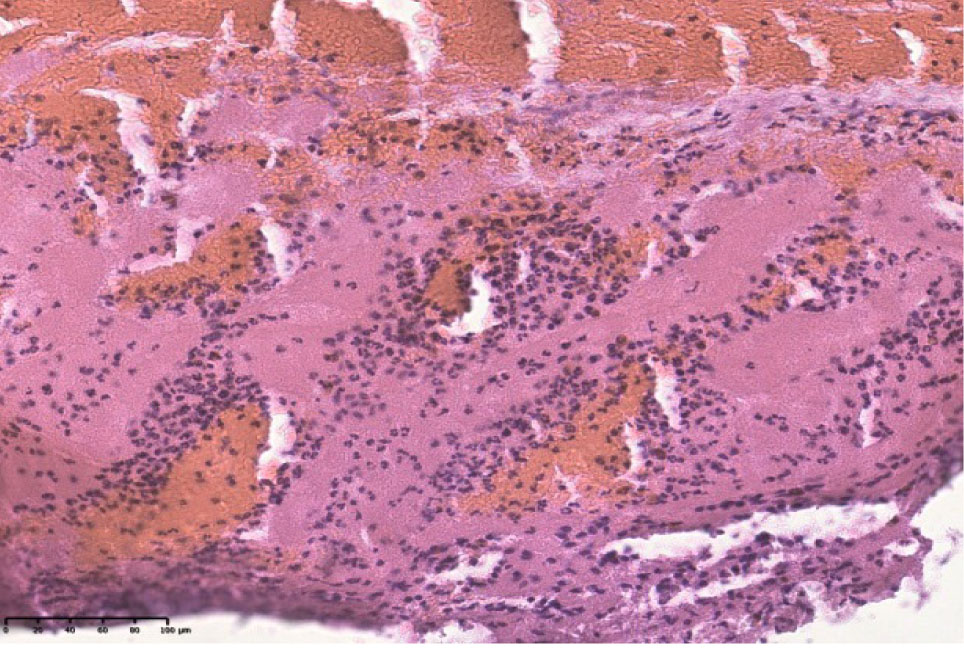

При повторном инфаркте миокарда в мышечных волокнах наблюдается значительное количество гипертрофированных кардиомиоцитов и гипотрофировавнных с отложениями зерен буро-коричневого цвета. Ярко выражены признаки кардиосклероза и кардиофиброза. В поле зрения визуализируются отечные мышечные волокна, лишенные поперечной исчерченности, гомогенезированые, ядра пораженных мышечных волокон сохранены, чаще пикноморфны. Наблюдаются кардиомиоциты в состоянии глыбчатого распада, участки некроза с пролиферацией клеток гистио- и фибробластического рада. Кровеносные сосуды полнокровные (рис. 1Б).

Рис. 1. Срез стенки сердца мужчины 67 лет (инфаркт миокарда) (А). Срез стенки сердца женщины 65 лет (повторный инфаркт миокарда) (Б). Окрашено гематоксилином и эозином.